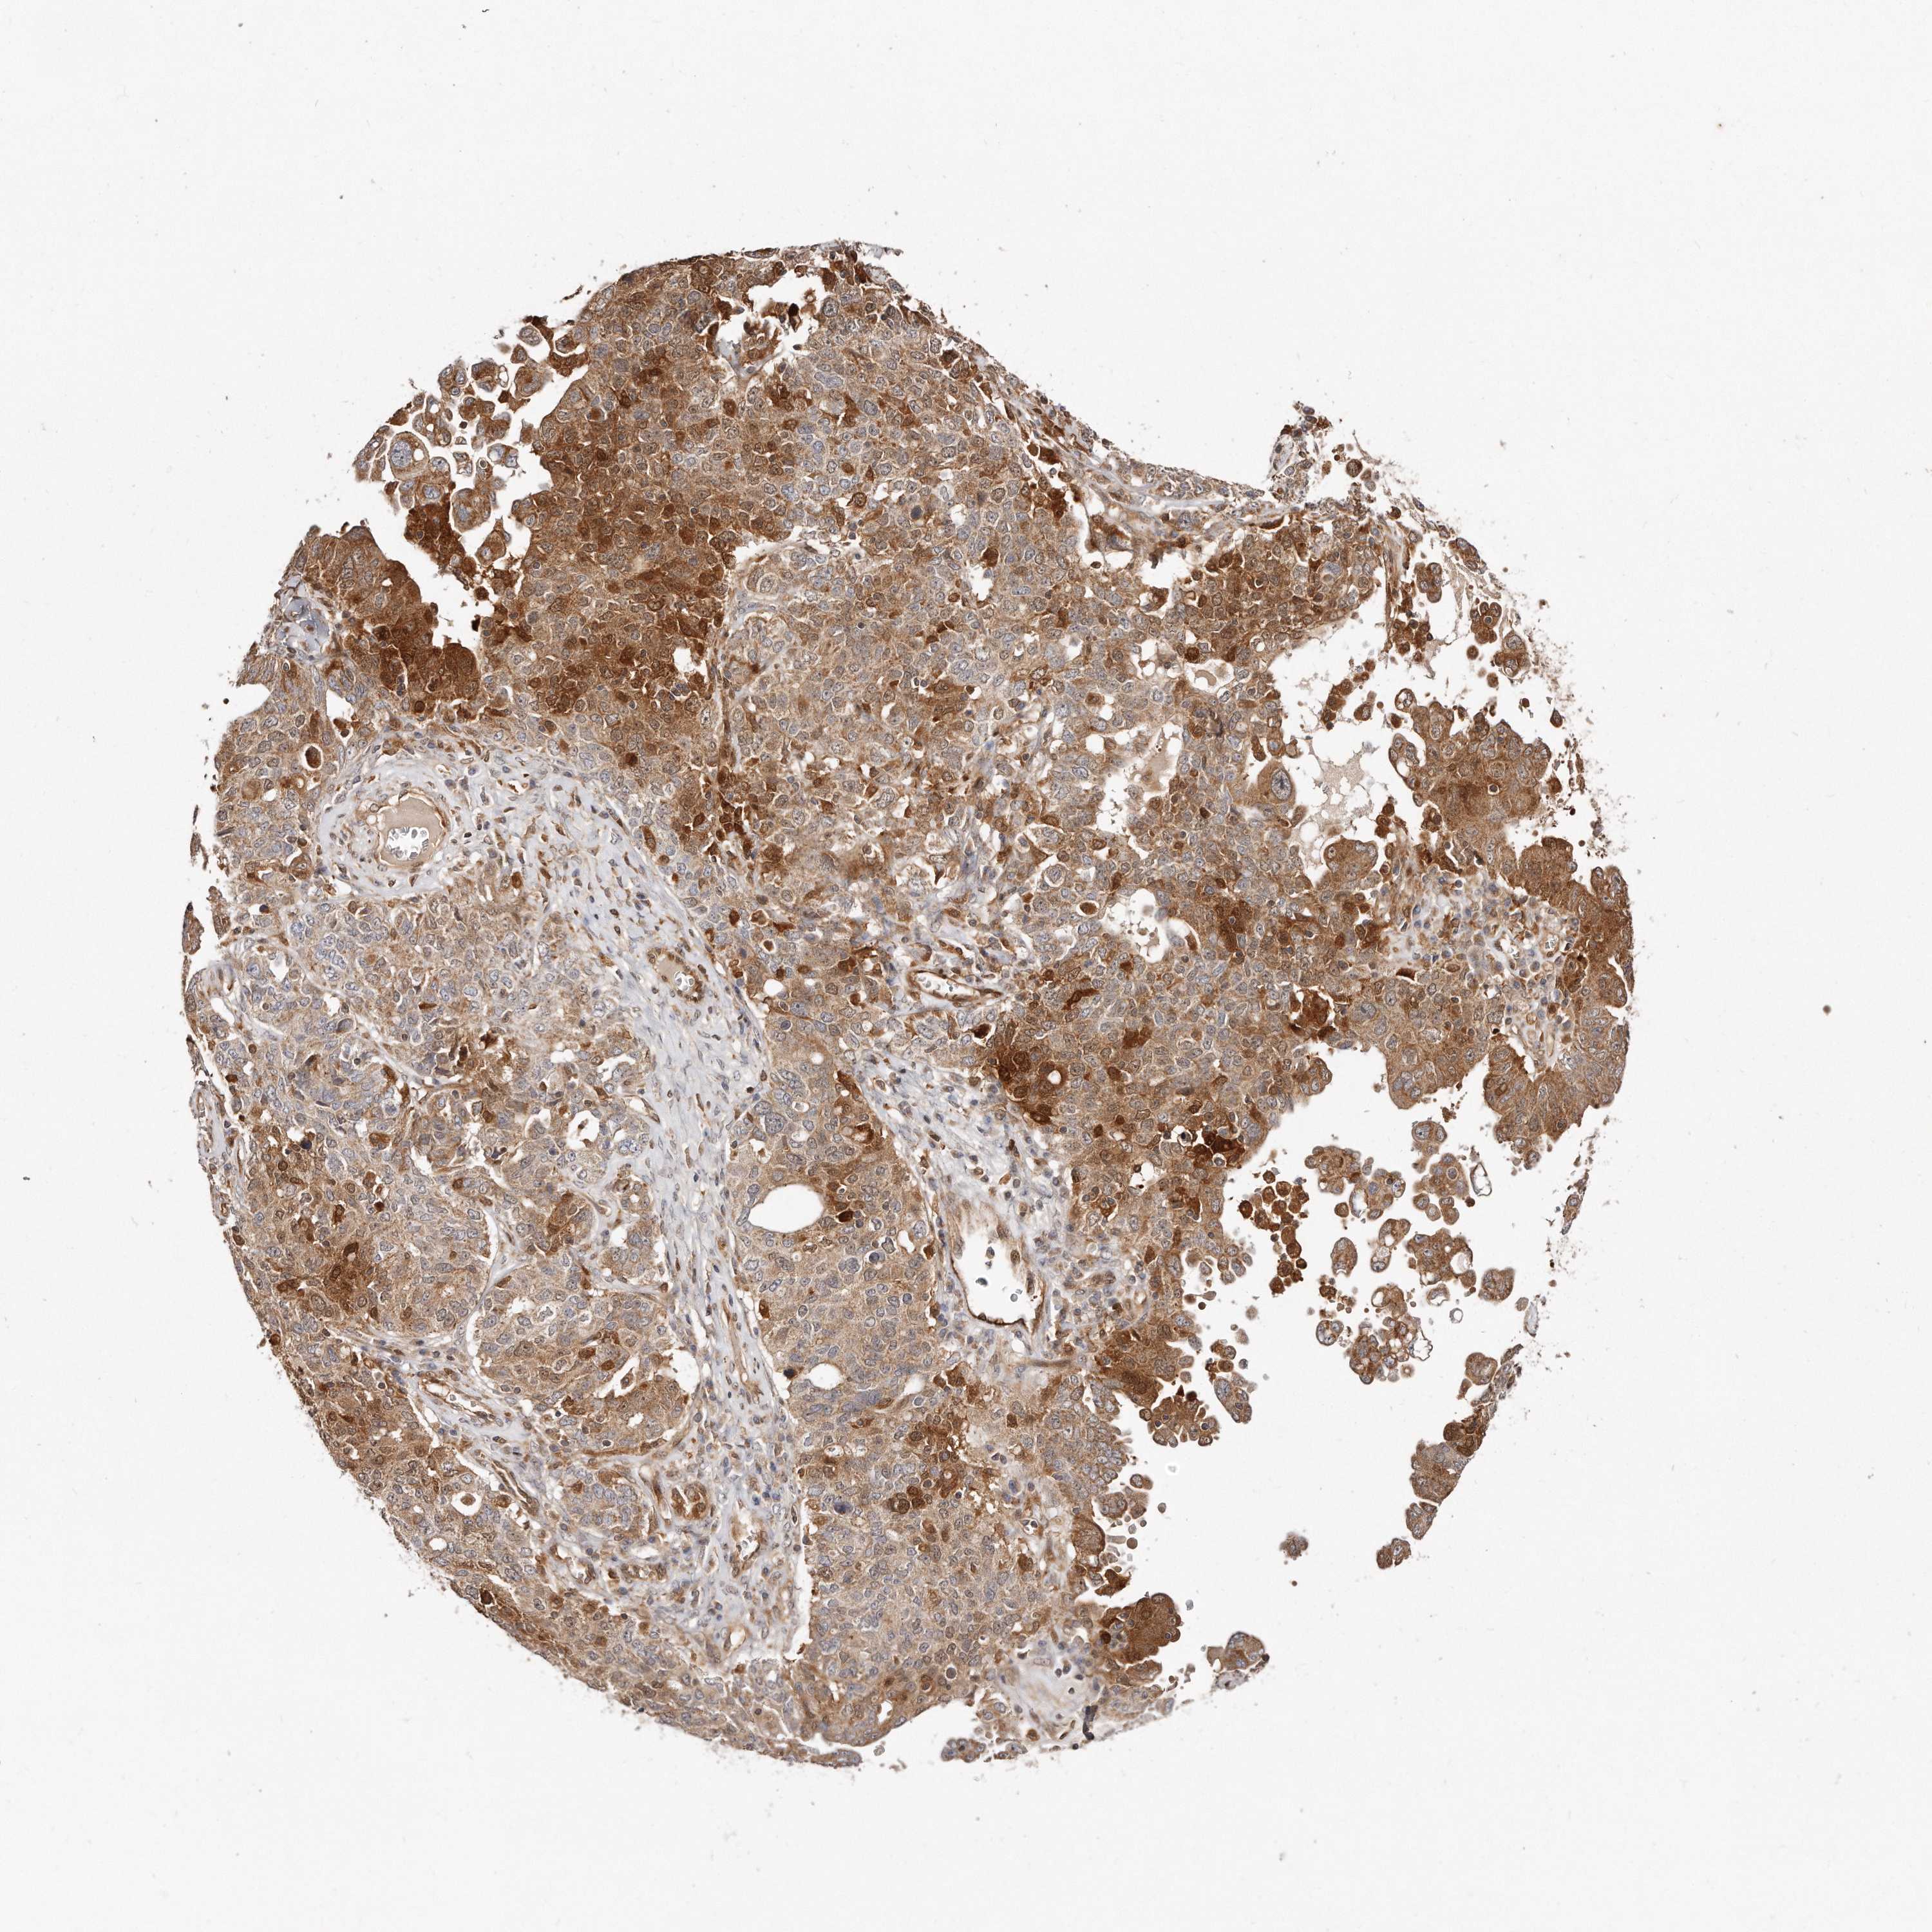

OVARIAN CANCER - Protein expressioni

A mouse-over function shows sample information and annotation data. Click on an image to view it in a full screen mode. Samples can be filtered based on level of antibody staining by selecting one or several of the following categories: high, medium, low and not detected. The assay and annotation is described here.

Note that samples used for immunohistochemistry by the Human Protein Atlas do not correspond to samples in the TCGA dataset.

Antibody stainingi

Antibody staining in the annotated cell types in the current human tissue is reported as not detected, low, medium, or high, based on conventional immunohistochemistry profiling in selected tissues. This score is based on the combination of the staining intensity and fraction of stained cells.

Each image is clickable and will lead to virtual microscopy that enables deeper exploration of all samples and also displays staining intensity scores, fraction scores and subcellular localization as well as patient and tissue information for each sample.

Antibody HPA030101

Staining

High

Medium

Low

Not detected

Intensity

Strong

Moderate

Weak

Negative

Quantity

>75%

75%-25%

<25%

None

Location

Nuclear

Cytoplasmic/membranous

Cytoplasmic/membranous,nuclear

Cystadenocarcinoma, serous, NOS

Carcinoma, endometroid

Cystadenocarcinoma, mucinous, NOS

Carcinoma, NOS